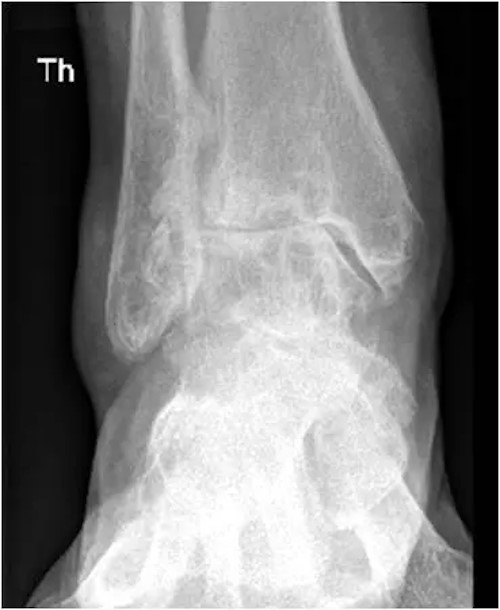

Das Röntgenbild des Sprunggelenkes in zwei Ebenen im Stand zeigt in fortgeschrittenen Fällen typische Arthrosezeichen:

• Gelenkspaltverschmälerung

• subchondrale Sklerosierung

• Exophyten

• Deformierung des Gelenkes

Röntgenbild einer OSG Arthrose mit starker Verschmälerung des Gelenkspalts

welche stadienabhängig unterschiedlich stark ausgeprägt sind.